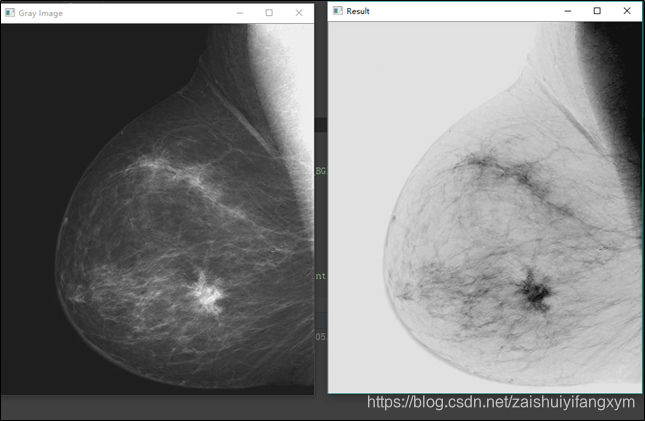

下图所示为图像反转的例子,原图像是数字乳房X射线照片,其中显示有一小块病变,通过图像反转就很容易看到病变区域。

运行结果如下图所示: